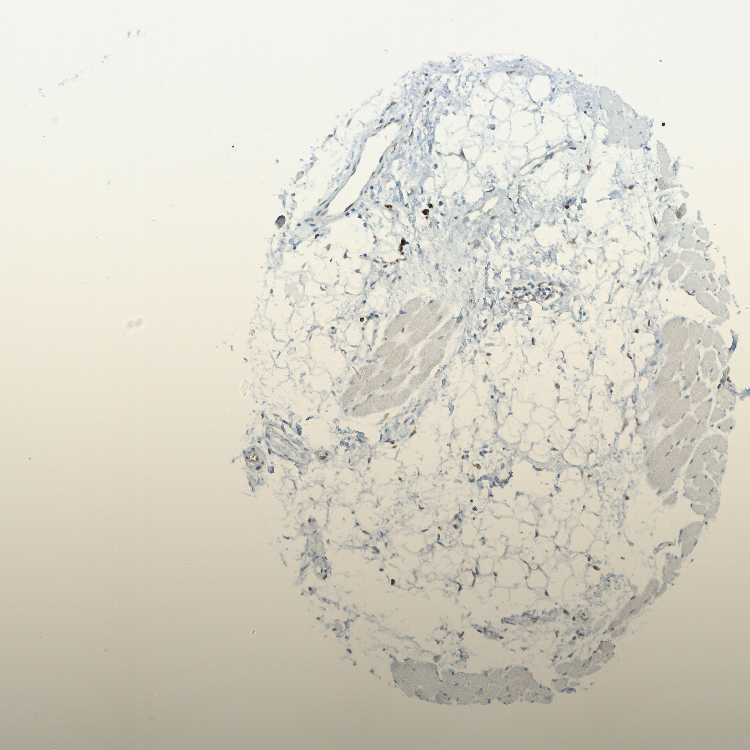

SKELETAL MUSCLE - Antibody stainingi

Antibody staining in the annotated cell types in the current human tissue is reported as not detected, low, medium, or high, based on conventional immunohistochemistry profiling in selected tissues. This score is based on the combination of the staining intensity and fraction of stained cells.

Each image is clickable and will lead to virtual microscopy that enables deeper exploration of all samples and also displays staining intensity scores, fraction scores and subcellular localization as well as patient and tissue information for each sample.

Antibody HPA011276Antibody HPA017062

Myocytes Not detectedNot detected